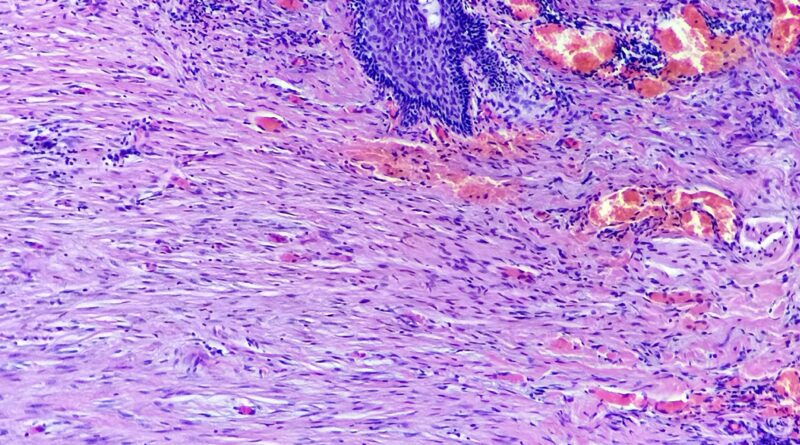

Pacjent 43 letni przyjęty w trybie planowym na Oddział Ortopedii z powodu wielomiesięcznego narastającego bólu, tkliwości, obrzęku i zmniejszenia ruchomości

Czytaj więcej